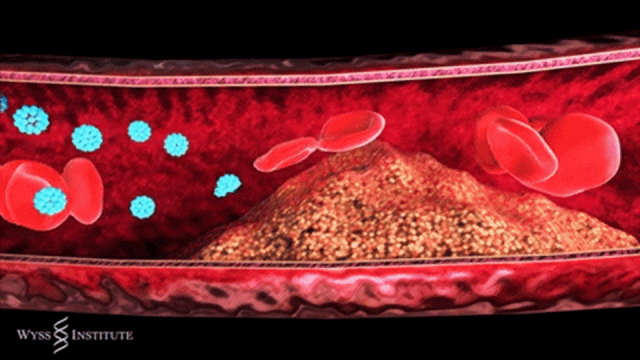

简单来说,动脉粥样硬化是血管壁的一场 “慢性病变”:血液中的脂质在血管壁沉积,伴随炎症反应不断发展,逐渐形成斑块。这些斑块会像 “水垢” 一样堵塞血管,让血流变慢,严重时甚至完全阻断血流,引发致命问题。

切片显示移植干细胞参与修复血管,向内皮细胞分化

间充质干细胞可以分化为内皮细胞,加速受损内皮修复,抑制动脉狭窄的形成。另外,体外输注的间充质干细胞能够向受损部位募集,并进一步分化为内皮细胞,修复损伤血管。